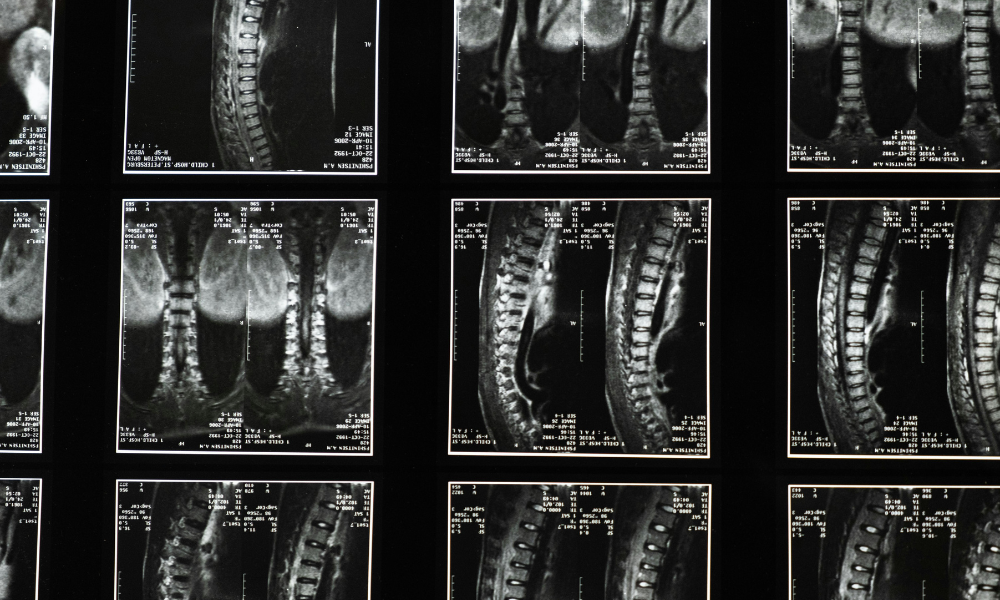

The trial involved four men over the age of 60 who had experienced severe spinal cord injuries two to four weeks prior to treatment. Each patient received an injection of two million donor-derived iPS cells directly into the site of injury. After a year of monitoring, researchers reported no serious side effects, including no evidence of tumour formation, which has historically been a concern with pluripotent stem cell therapies. Two of the four patients demonstrated measurable neurological improvement, suggesting that the treatment may be effective in a subset of patients.